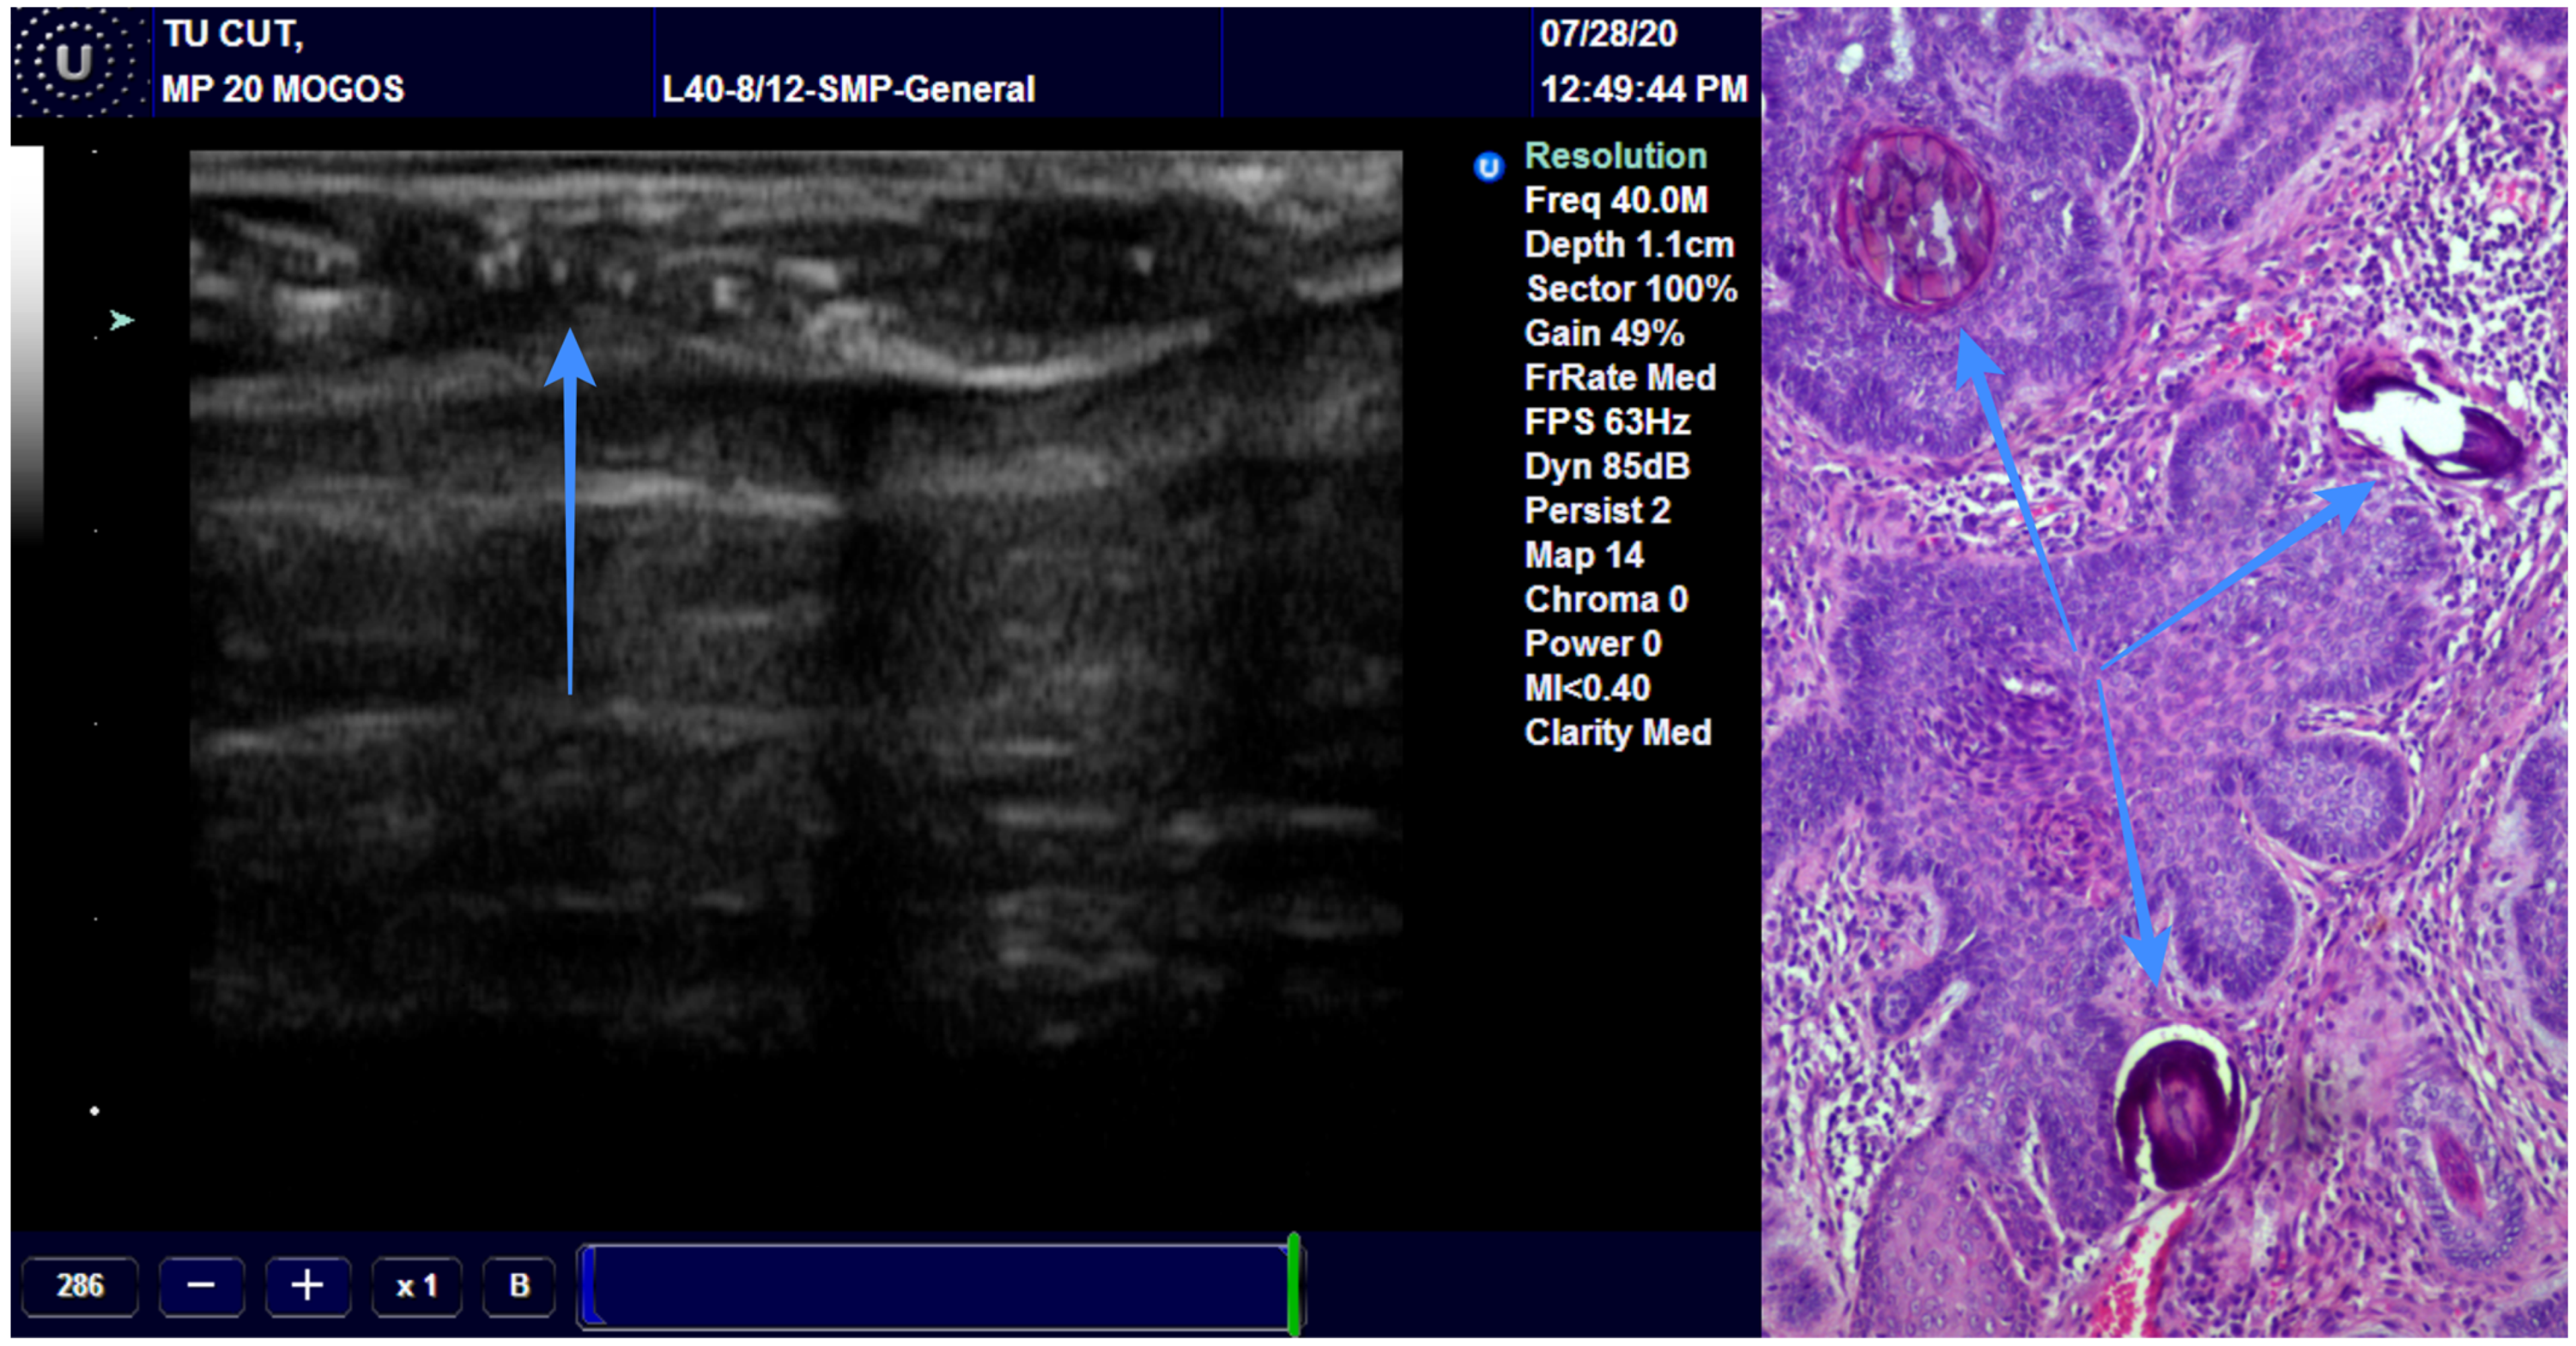

We assessed the concordance between the final diagnosis and ultrasound diagnosis, and we found a Cohen’s Kappa of 0.8897 (95% CI: 0.6783–1.1011), bias-adjusted Kappa of 0.8895 and prevalence- and bias-adjusted Kappa of 0.9355 (Table 3). The concordance between the final diagnosis of BCC and the presence of hyperechoic spots followed an identical pattern. We have associated the presence of the hyperechoic spots with diagnosis of BCC (Figure 4). Only one case of BCC was misdiagnosed by echography due to the missing hyperechoic spots (Figure 5).

Figure 4.

The arrow is showing the presence of the hyperechoic spots in a BCC and the pathological correspondence.

Figure 5.

Misdiagnosed BCC due to the absence of hyperechoic spots.

The incisional biopsy is done for the big lesions but is very difficult or impossible to achieve in the case of small lesions. For these lesions, an excisional biopsy with wide margins is used for diagnosis and also for treatment. Mohs surgery can help for diagnosis and proper treatment of skin cancer. On ultrasound, the BCC and SCC look quite similar, except the BCC presents some hyperechoic spots. They look like a cotton flower but the particularity is the absence of the acoustic shadowing [35]. The spots are histologically represented by microcalcifications, horn cysts and apoptotic cells. Alfageme Roldan F has studied these spots and he found two interesting aspects: the increased number of spots is associated with an aggressive behavior and the micronodular type presents the highest number of spots. These results could be very useful in the diagnosis process and treatment plan [36]. In accordance with the other studies, we found an excellent correlation between the presence of hyperechoic spots and the diagnosis of BCC. We recommend this method for differentiating the BCC from other skin malignancies and for avoiding extending the surgical excision unnecessarily.